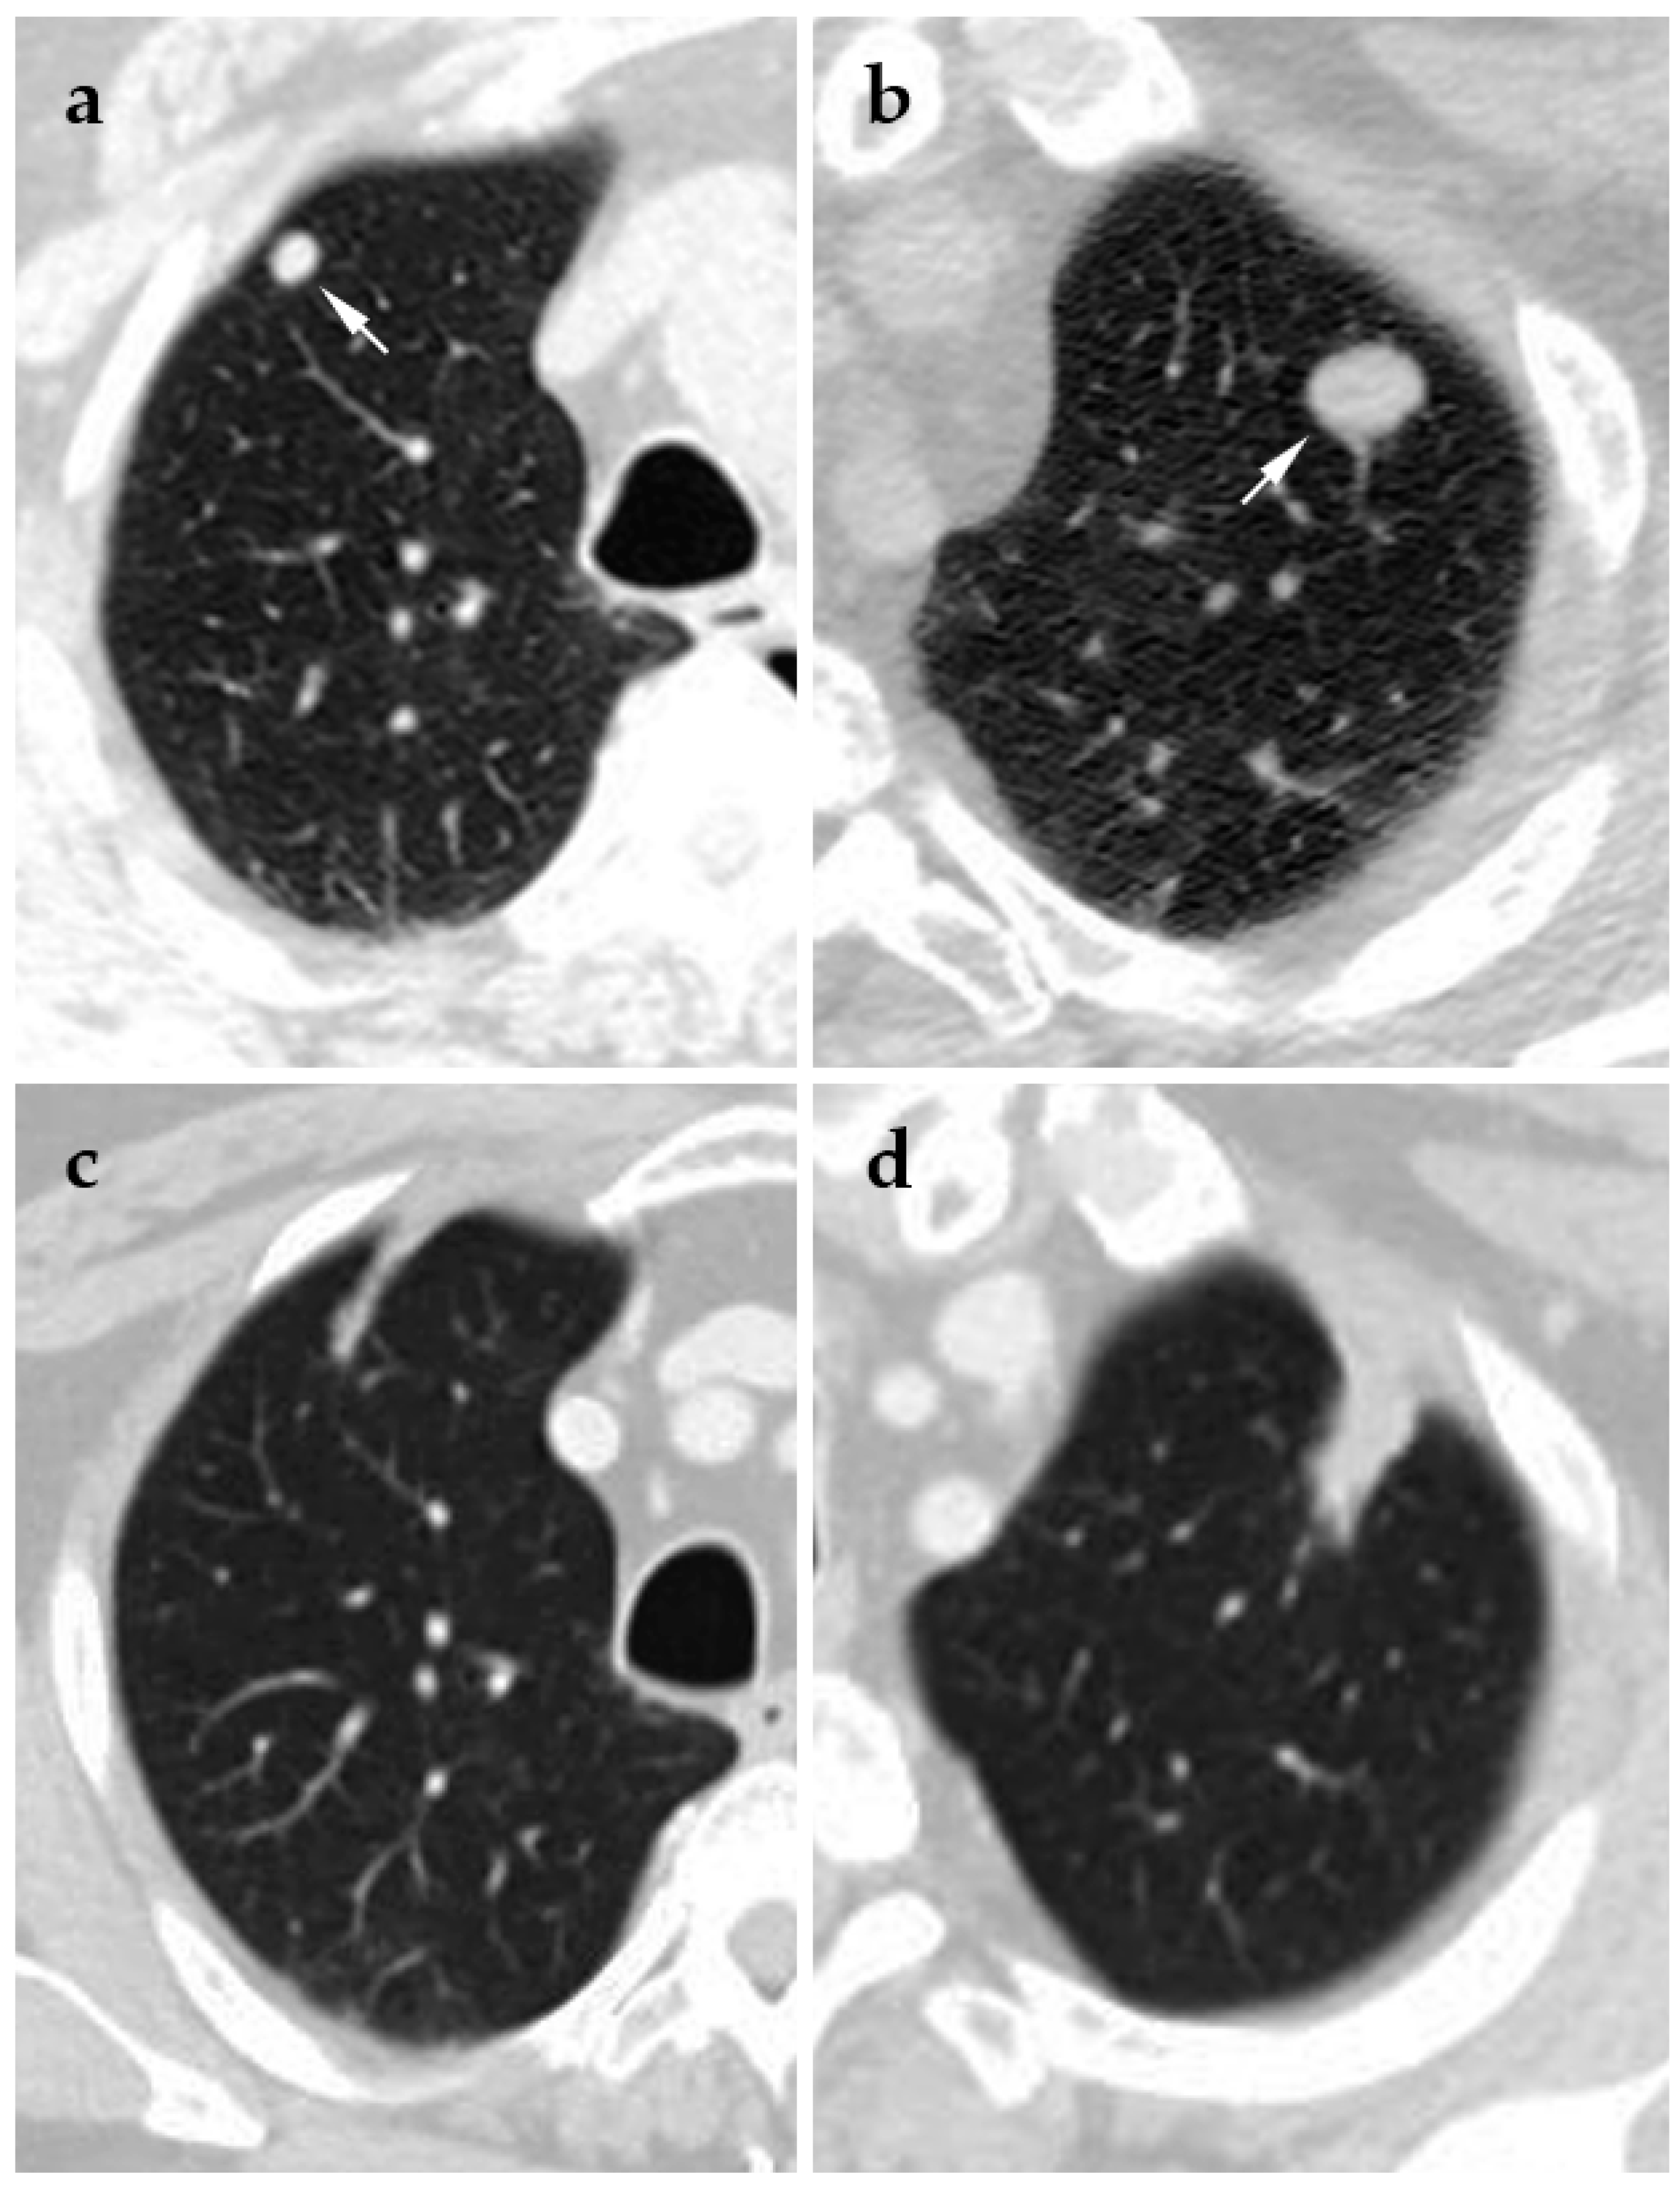

- Chheang, S.; Abtin, F.; Guteirrez, A.; Genshaft, S.; Suh, R. Imaging features following thermal ablation of lung malignancies. Semin. Intervent. Radiol. 2013, 30, 157–168. [Google Scholar] [CrossRef] [PubMed]